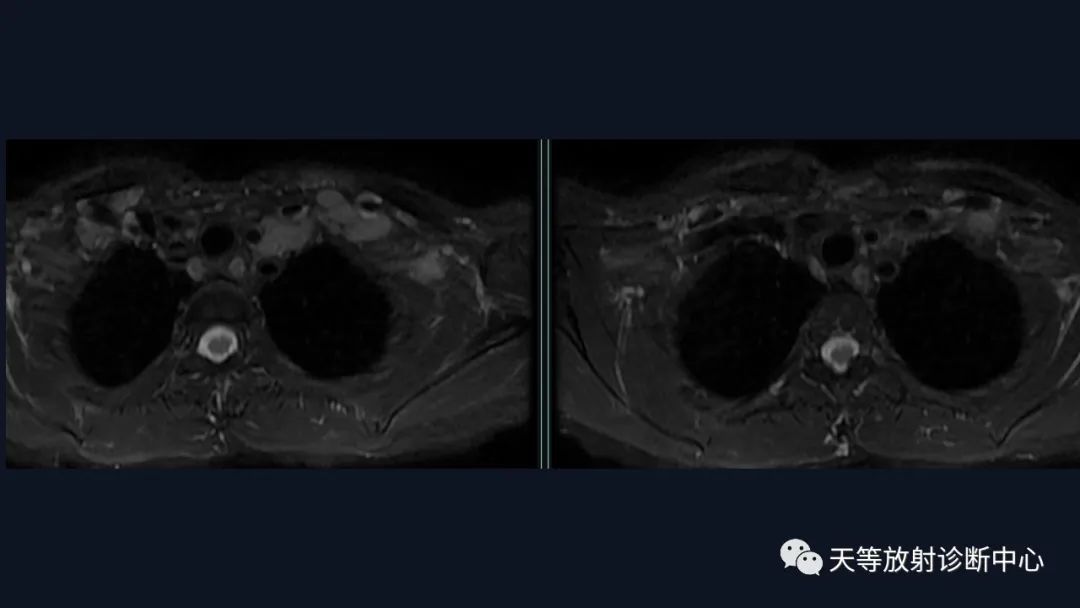

本病例影像学特点:

脑内占位的特点:

结合颈部、胸廓入口区及腋窝多发淋巴结肿大并相互融合。

综合考虑淋巴瘤